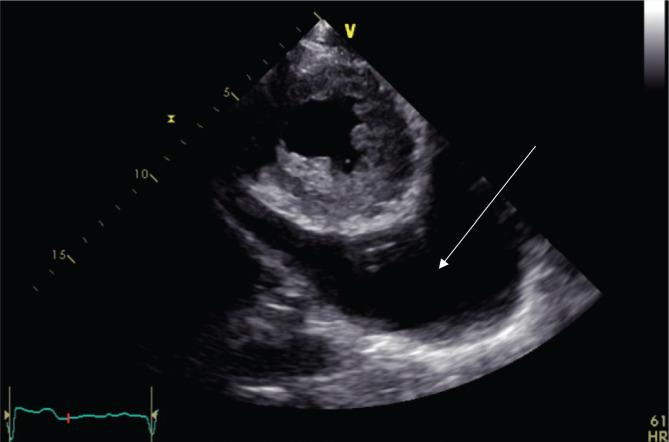

Pericardial effusion can either be an incidental finding or a manifestation of systemic or cardiac disease. It has a wide range of presentations, from asymptomatic small effusion to rapidly progressive fatal tamponade. In a trauma setting, pericardial effusion is usually attributed to hematoma collection, with the concern of clinical evidence of tamponade that can lead to cardiopulmonary collapse. The Focused Assessment with Sonography for Trauma (FAST) is a widely used tool to diagnose pericardial effusion in trauma patients. We published this case report to emphasize that the presence of pericardial effusion alone in a trauma patient does not indicate the presence of tamponade. This case concerns a 39 years old male patient who presented to ER as a trauma case after a fall from two meters height and landing on his feet. ATLS protocol was followed, and FAST showed an incidental finding of massive pericardial fluid. The trauma team was consulted, and the patient was hemodynamically stable without clinical evidence of tamponade. Echocardiography showed mitral valve stenosis and large pericardial effusion. The close observation did not suggest the presence of cardiac tamponade. The pericardial catheter was inserted during admission with drainage of 900cc of serous fluid. The presence of pericardial fluid in a trauma setting does not confirm the diagnosis of tamponade. The mechanism of injury, clinical presentation, and the patient's stability are essential factors in determining further management of such patients.

心包积液可以是偶然发现,也可以是全身性或心脏疾病的表现。它的表现范围很广,从轻症无症状的少量积液到迅速进展的致命填塞不等。在创伤环境中,心包积液通常归因于血肿积聚,同时还需要关注是否存在填塞的临床证据,因为这可能导致心肺衰竭。创伤超声重点评估(FAST)是一种广泛用于诊断创伤患者心包积液的工具。我们发表这个病例报告是为了强调,在创伤患者中,仅仅存在心包积液并不表明存在填塞。本病例涉及一名 39 岁男性患者,他从两米高处坠落,双脚着地后被送往急诊室作为创伤病例。遵循 ATLS 方案,FAST 显示大量心包积液的偶然发现。创伤小组进行了会诊,患者血流动力学稳定,没有填塞的临床证据。超声心动图显示二尖瓣狭窄和大量心包积液。密切观察并未提示存在心脏填塞。入院时插入心包导管,引流 900cc 浆液性液体。在创伤环境中存在心包积液并不能确诊为填塞。损伤机制、临床表现和患者的稳定性是决定此类患者进一步治疗的重要因素。